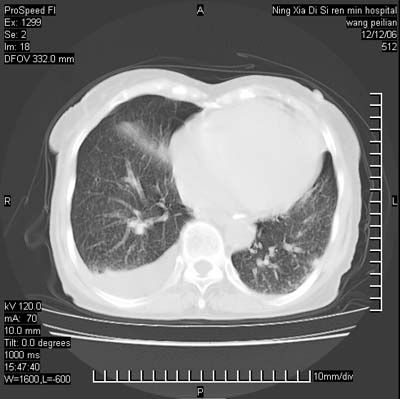

标题: CT5609:胸部:女77 病史不详

两肺可见多个大小不等的结节,左侧有胸水,纵隔淋巴结增大,考虑是细支气管肺泡癌

两肺尖纤维索状影,两下肺结节块状影,且有钙化灶,右胸腔积液。考虑肺结核并胸膜炎。

两肺尖纤维索状影,两下肺结节块状影,且有钙化灶,右胸腔积液。考虑肺结核并胸膜炎肺间质纤维化

考虑:1、慢性支气管炎合并全小叶型肺气肿、间质纤维化;

2、双肺结核;

3、右侧胸膜炎(积液)。

1、双肺继发型肺结核(以纤维、增殖灶为主);

2、右侧胸腔积液;

3、其余符合老年肺改变。

双肺见多个结节状及条索状影,双侧胸腔积液,右侧叶间积液,考虑结核性胸膜炎